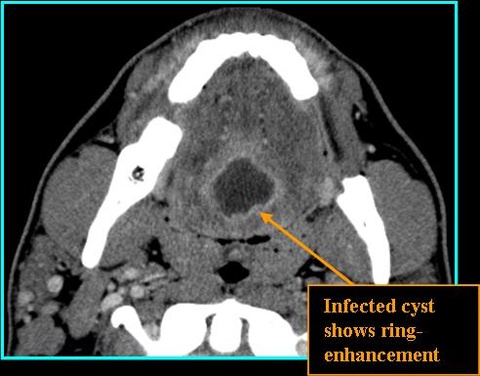

- On CT: benign appearing, low-density, occasionally septated, thin rim of peripheral enhancement with contrast, thicker rim if infected